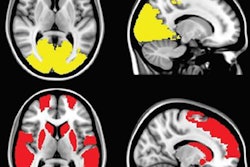

More specifically, the group with high blood pressure showed lower fractional anisotropy values in brain fibers in the anterior thalamus, affecting nonverbal skills; nerve fibers in the superior longitudinal fasciculus, which are involved with executive function and regulating emotions; and limbic system fibers of the cingulate gyrus, which are associated with attention tasks.

DTI-MRI illustrates the main tracts affected by hypertension. Reconstruction shows lower fractional anisotropy levels in regions including the anterior thalamic radiations, superior longitudinal fasciculus, and cingulate gyrus, resulting in significant deterioration in hypertensive patients. Image courtesy of Daniela Carnevale, PhD.And, if that wasn't enough, MRI scans also confirmed damage to the heart and kidneys among members of the high blood pressure group.